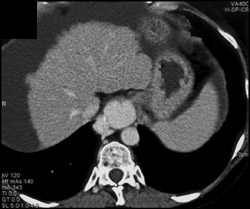

Diagnosis

Hepatoma